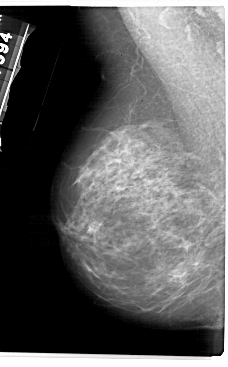

A_1944_1.LEFT_CC

LEFT_CC LINES 5431 PIXELS_PER_LINE 3106 BITS_PER_PIXEL 12 RESOLUTION 43.5 NON_OVERLAY